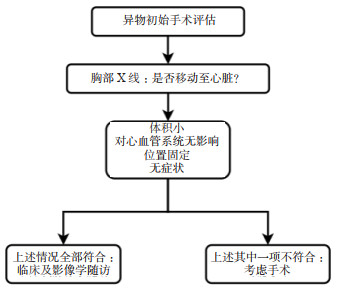

1 资料与方法患者男性,17岁,因“左前臂异物8 h”于2022-05-23 21:25收住急诊抢救室。患者8 h前修车时敲打金属物品,小片金属飞溅至左前臂,伴少量出血,无麻木等不适主诉。后立即于当地医院就诊,X线示异物位置如图 1,当地医院建议转上级医院。上级医院再次行X线检查(图 2),后予以臂丛麻醉下行“左上肢清创+异物取出术”术中未见异物,术后复查X线,左上肢,左肩部以及左侧胸部未见异物,嘱立即转至本院。

| 图 1 外伤后第一次评估异物位置X光检查图像 |